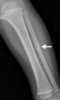

Thick periosteal reaction along bone shaft

May Be Caused by